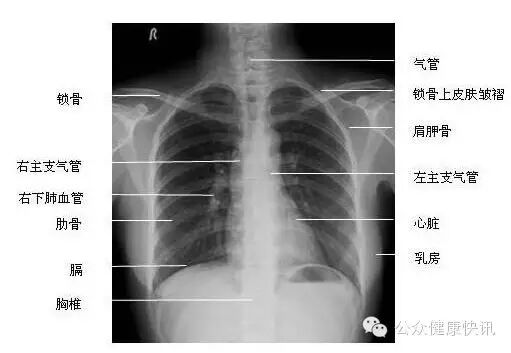

这是胸片正常的情况。

主要用于肺炎行实变、纤维化、钙化、肿块、肺不张肺间质病变肺气肿、空洞、支气管炎症及扩张、胸腔积液气胸胸膜肥厚粘连、纵膈肿瘤、心脏、血管性态、乳房肿块诊断。